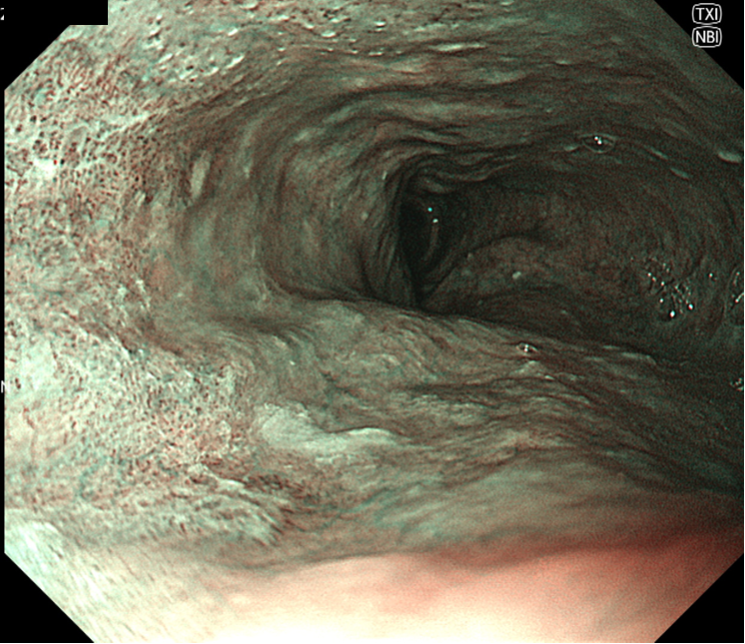

• NBI+TXI観察(中遠景)

切替前 NBI強調設定:B8

NBI+TXIレベル:中

図4 TXI咽頭

咽頭部全体を明瞭に観察できる。